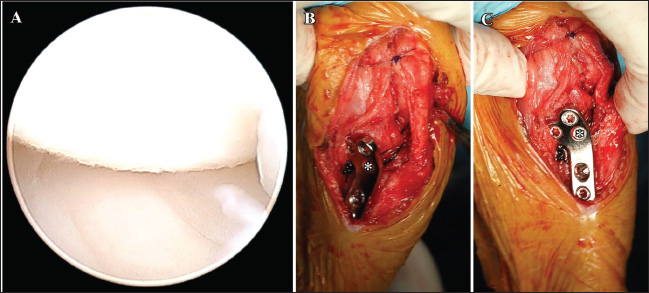

Fig. 2. Ultrasonography of the right stifle joint at the first visit. Complete rupture of the cranial cruciate ligament (arrow, A) and severe joint effusion (asterisk, B) can be observed. Although the medial buttress (arrow, C) can be visualized, the caudal horn of medial meniscus shows no damages (C). CCL=cranial cruciate ligament; F=femur; M=medial meniscus; P=patella; T=tibia.

Fig. 5. Ultrasonography of the left stifle joint at 8 weeks after surgery on the right limb. The joint shows complete rupture of cranial cruciate ligament (arrow, A), moderate joint effusion (asterisk, B), and the medial buttress (arrow, C). The caudal horn of medial meniscus shows no injury (C). CCL=cranial cruciate ligament; F=femur; M=medial meniscus; P=patella, T=tibia.

Fig. 6. Arthroscopic image of the medial meniscus and LFTS following the TPLO plate placement on the left limb. The medial meniscus is intact (A). The nylon suture is passed around the lateral femoral fabella. Both ends of the suture are passed under the patella ligament. One end of the suture is passed proximally, and the other end of the suture is passed distally to the cranial screw (asterisk) under the TPLO plate (B and C). The surgeon’s knot is ligated on the caudal side of the TPLO plate (arrow, C). F=femur; M=medial meniscus; T=tibia. A bone tunnel is typically created in the tibial tuberosity to facilitate the passage of the LFTS strand (Knight and Danielski, 2018). The spatial flexibility of the tibia following installation of the TPLO plate in toy-breed dogs is less than that observed in middle and large-breed dogs. The bone tunnel could increase the incidence of side effects such as tibial tuberosity fractures. To minimize iatrogenic risks, we employed the modified LFTS technique described earlier. This fixation strategy may provide a feasible substitute in small dogs where traditional tunnel-based techniques pose a higher complication risk. We applied No. 3 monofilament nylon suture owing to its documented tensile strength and established suitability for extracapsular stabilization in small-breed dogs. The application of LFTS alone may require a stronger strand or a greater number of strands. However, the TPLO plate had already controlled the cranial tibial thrust. Therefore, we selected the No. 3 suture, which provides tensile strength nearly double the dog’s body weight. The combination of TPLO and LFTS procedures is associated with an increased risk of complications, such as infection or tibial tuberosity fractures (Schaible et al., 2017). Furthermore, suture materials, such as nylon, placed around the joint during LFTS, could increase the possibility of infection compared with a single TPLO. Persistent postoperative lameness caused by implant infection potentially requires a second surgery to remove the implant. In this case, antibiotics were administered for 5 days post-surgery to prevent infection. Although the placement TPLO plate and the single strand of the LFTS could enhance stifle joint stability with CCLR, further studies must be conducted to determine the specific cause of the pivot shift phenomenon post-TPLO in toy breeds. In addition, the single stand of the LFTS demonstrated sufficient strength to maintain the stability of the stifle joint for up to 5 months after the TPLO surgery in dog weighing under 6 kg. However, stronger LFTS materials such as thicker sutures or double strands may need to guarantee adequate stabilization in toy-breed dogs weighing over 6-kg toy-breed dogs. As this report describes only a single case, additional case studies in toy-breed dogs are necessary to establish appropriate LFTS materials and fixation methods. ConclusionThe findings of this report indicate that the combination of TPLO and LFTS effectively restores the stability of the stifle joint in large and toy-breed dogs. To the best of our knowledge, this is the first report to demonstrate the effectiveness of the combination of TPLO and LFTS in toy-breed dogs (<6 kg) with CCLR. AcknowledgmentsWe would like to thank Editage (www.editage.com) for its English language editing services. Conflict of interestThe authors declare no conflicts of interest. FundingThis work was supported by Rakuno Gakuen University. Author’s contributionsNam ER and Honnami contributed equally to this study. Conceptualization: Nam ER, Honnami M; Data curation: Nam ER, Honnami M; Funding acquisition: Nam ER; Methodology: Honnami M, Amano M; Supervision: Mochizuki M; Writing—original draft: Nam ER; Writing—review and editing: Nam ER, Honnami M. Data availabilityAll data supporting the findings of this study are available within the manuscript. ReferencesBoudrieau, R.J. 2009. Tibial plateau leveling osteotomy or tibial tuberosity advancement? Vet. Surg. 38, 1–22. Brioschi, V. and Arthurs, G.I. 2021. Cranial cruciate ligament rupture in small dogs (<15 kg): a narrative literature review. J. Small Anim. Pract. 62, 1037–1050. Bureau, S. 2017. Owner assessment of the outcome of tibial plateau levelling osteotomy without meniscal evaluation for treatment of naturally occurring cranial cruciate ligament rupture: 130 cases (2009 to 2013). J. Small Anim. Pract. 58, 468–475. Comerford, E., Forster, K., Gorton, K. and Maddox, T. 2013. Management of cranial cruciate ligament rupture in small dogs: a questionnaire study. Vet. Comp. Orthop. Traumatol. 26, 493–497. Fujino, H., Honnami, M. and Mochizuki, M. 2020. Preoperative planning for tibial plateau leveling osteotomy based on proximal tibial width. J. Vet. Med. Sci. 82, 661–667. Gatineau, M., Dupuis, J., Planté, J. and Moreau, M. 2011. Retrospective study of 476 tibial plateau levelling osteotomy procedures. Rate of subsequent ‘pivot shift’, meniscal tear and other complications. Vet. Comp. Orthop. Traumatol. 24, 333–341. Harasen, G. 2008. Canine cranial cruciate ligament rupture in profile: 2002–2007. Can. Vet. J. 49, 193–194. Kim, S.E., Lewis, D.D. and Pozzi, A. 2012. Effect of tibial plateau leveling osteotomy on femorotibial subluxation: in vivo analysis during standing. Vet. Surg. 41, 465–470. Knight, R. and Danielski, A. 2018. Long-term complications following tibial plateau leveling osteotomy in small dogs with tibial plateau angles > 30°. Vet. Rec. 182, 461. Knight, R.C., Thomson, D.G. and Danielski, A. 2017. Surgical management of pivot-shift phenomenon in a dog. J. Am. Vet. Med. Assoc. 250, 676–680. Kwananocha, I., Akaraphutiporn, E., Upariputti, R., Lekchareonsuk, C. and Wangdee, C. 2024. Short-term outcomes of cranial cruciate ligament rupture treated surgically with tibial plateau leveling osteotomy or nonsurgically in small-breed dogs weighing less than 10 kg. J. Vet. Med. Sci. 86, 428–435. Pozzi, A., Kowaleski, M.P., Apelt, D., Meadows, C., Andrews, C.M. and Johnson, K.A. 2006. Effect of medial meniscal release on tibial translation after tibial plateau leveling osteotomy. Vet. Surg. 35, 486–494. Schaible, M., Ben-Amotz, R., Caceres, A., Payton, M., Segev, Y. and Shani, J. 2017. Combined tibial plateau leveling osteotomy and lateral patellotibial suture for cranial cruciate ligament rupture with severe rotational instability in dogs. J. Small Anim. Pract. 58, 219–226. Schuenemann, R. and Kaczmarek, J. 2023. Tibial Plateau Leveling Osteotomy in small and large breed dogs: a comparative retrospective study of complications and outcomes. Tierarztl. Prax. Ausg. K. Kleintiere Heimtiere. 51, 6–14. Thieman, K.M., Tomlinson, J.L., Fox, D.B., Cook, C. and Cook, J.L. 2006. Effect of meniscal release on the rate of subsequent meniscal tears and owner-assessed outcome in dogs with cruciate disease treated with tibial plateau leveling osteotomy. Vet. Surg. 35, 705–710. Tikekar, A., De Vicente, F., McCormack, A., Thomson, D., Farrell, M., Carmichael, S. and Chase, D. 2022. Retrospective comparison of outcomes following tibial plateau levelling osteotomy and lateral fabello-tibial suture stabilisation of cranial cruciate ligament disease in small dogs with high tibial plateau angles. N. Z. Vet. J. 70, 218–227. Wheeler, J.L., Cross, A.R. and Gingrich, W. 2003. In vitro effects of osteotomy angle and osteotomy reduction on tibial angulation and rotation during the tibial plateau-leveling osteotomy procedure. Vet. Surg. 32, 371–377. Witte, P.G. 2015. Tibial anatomy in normal small breed dogs including anisometry of various extracapsular stabilizing suture attachment sites. Vet. Comp. Orthop. Traumatol. 28, 331–338. | ||